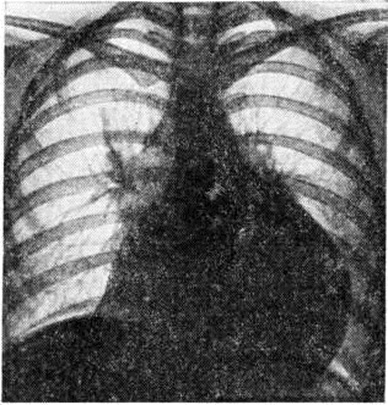

Рис. 5.

Рентгенограмма грудной клетки больного экссудативным перикардитом: тень сердца увеличена в поперечном размере, дуги плохо дифференцируются, форма сердца трапециевидная.